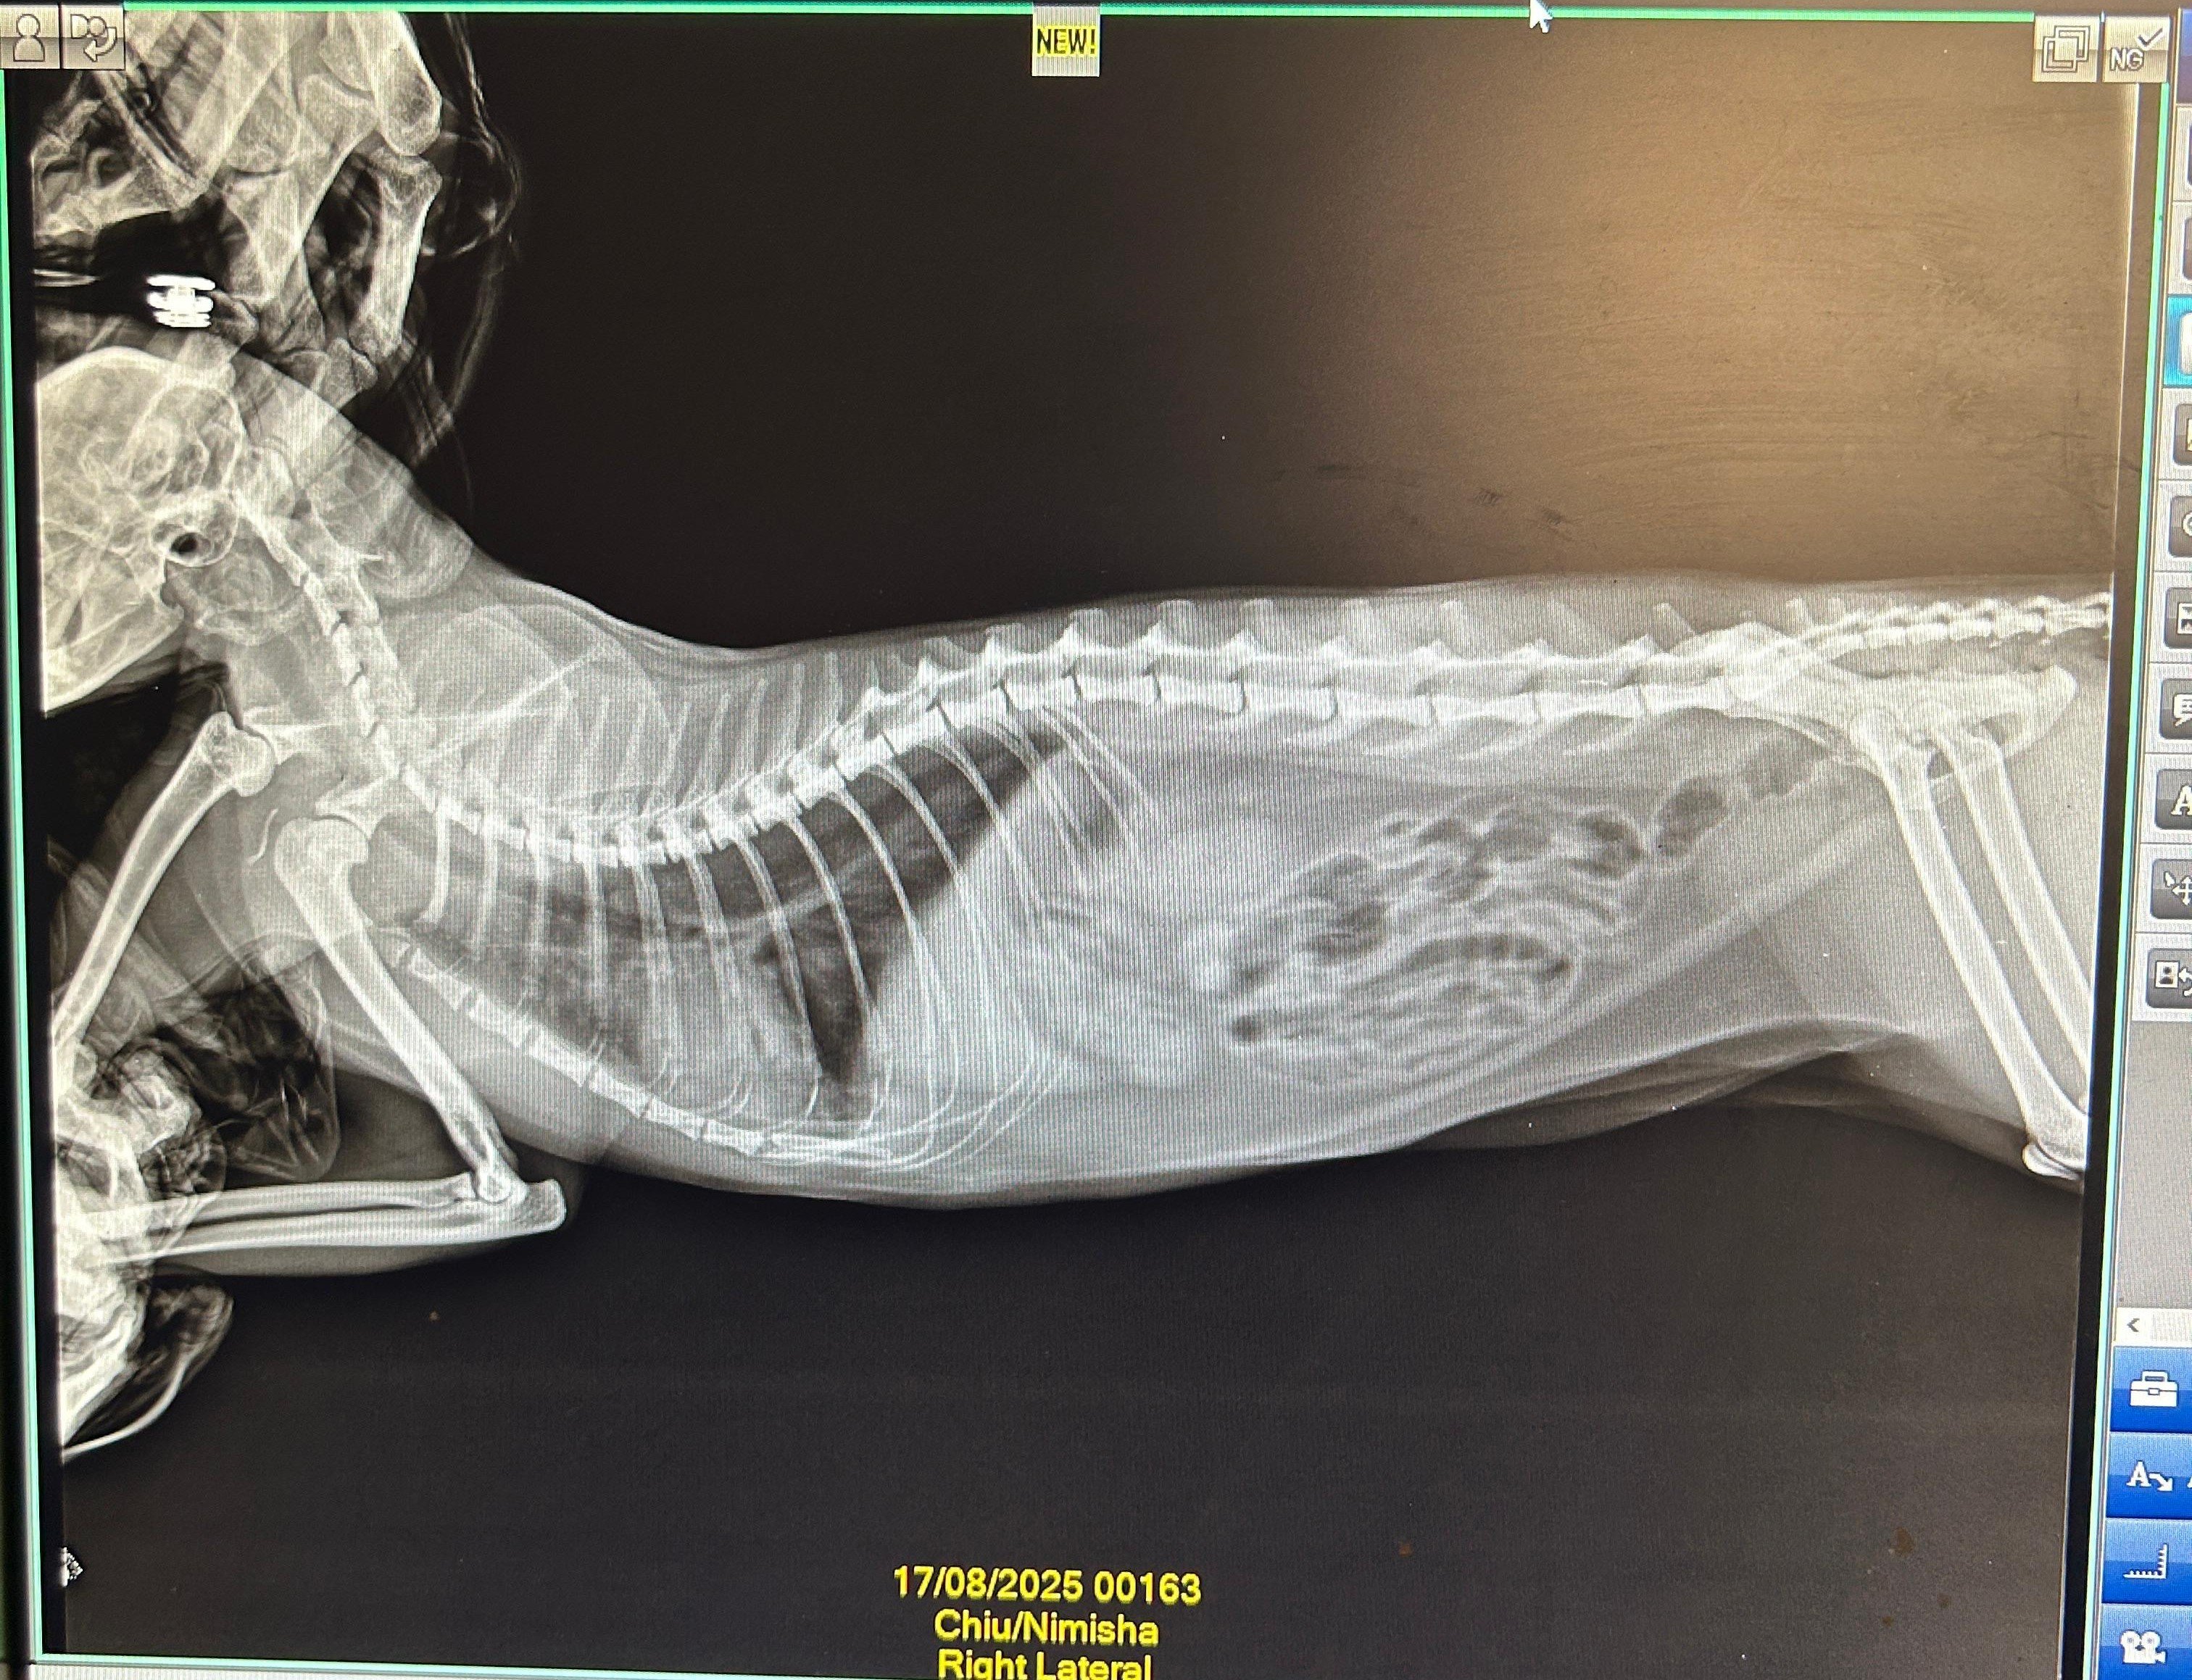

In early August, we got a repeat x-ray (attached) done which still showed bronchial lung pattern. She got Lasix and Penetrat (similar to Frenzyme). She stayed ok for about a month before symptoms returned.

4.1 Xray - RT LAT - Chiu - 20Dec2025.jpeg2.4 MB · Views: 43 -